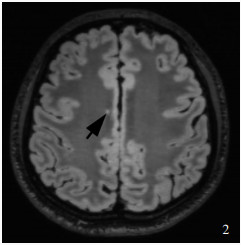

Berginström N , Nordström P , Nyberg L , Nordström A . White matter hyperintensities increases with traumatic brain injury severity: associations to neuropsychological performance and fatigue. Brain Inj, 2020, 34: 415- 420.

Chan A , Ai E , Gugger J , Walter A , Xu E , Kim A , Diaz-Arrastia R . Prevalence and location of white matter hyperintensities in traumatic brain injury and relationship to outcome (S15.005). Neurology, 2022, 98 (18-Sup): 2.

Jarrett M , Tam R , Hernández-Torres E , Martin N , Perera W , Zhao Y , Shahinfard E , Dadachanji S , Taunton J , Li DK , Rauscher A . A prospective pilot investigation of brain volume, white matter hyperintensities, and hemorrhagic lesions after mild traumatic brain injury. Front Neurol, 2016, 7: 11.

Clark AL , Sorg SF , Schiehser DM , Luc N , Bondi MW , Sanderson M , Werhane ML , Delano-Wood L . Deep white matter hyperintensities affect verbal memory independent of PTSD symptoms in veterans with mild traumatic brain injury. Brain Inj, 2016, 30: 864- 871.